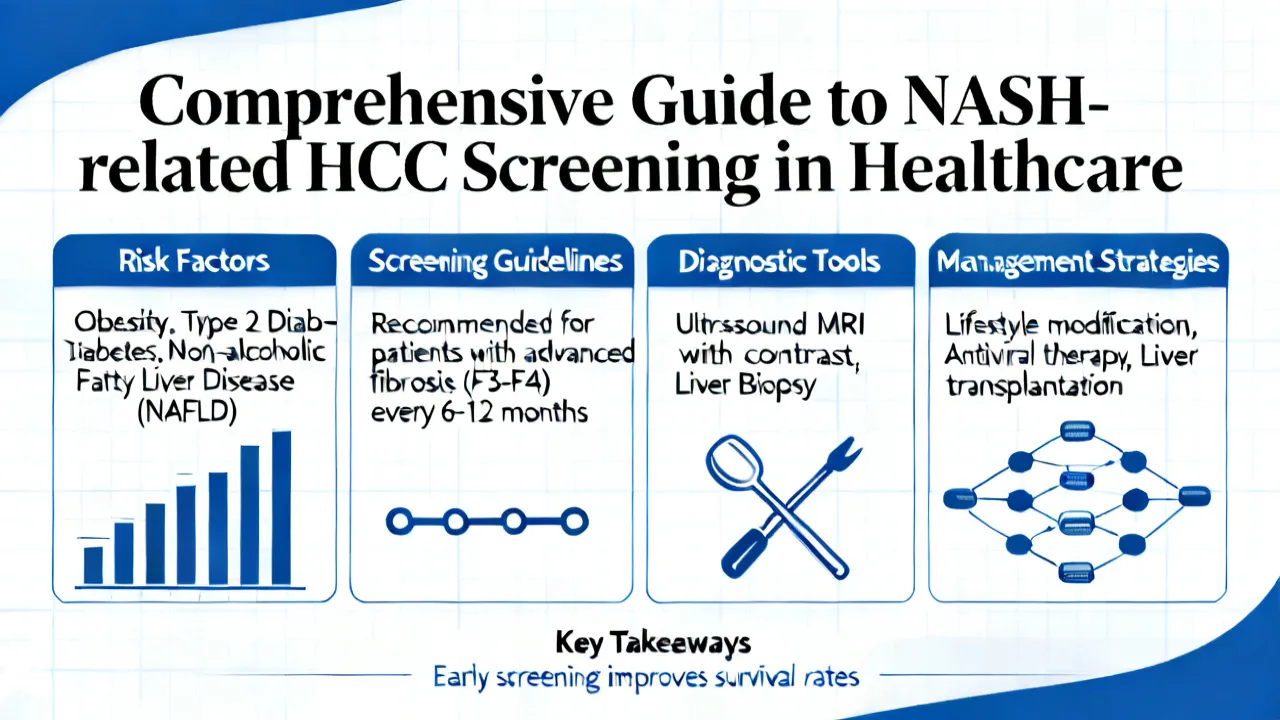

NASH HCC Screening is crucial for early detection and management of liver complications such as non-alcoholic steatohepatitis and hepatocellular carcinoma. Screening helps in identifying individuals at risk before symptoms develop. With advancements in medical technology, screening has become more precise, providing hope for better therapeutic outcomes and patient care in the ongoing battle against liver diseases.

NASH HCC screening plays a crucial role in the early detection of liver cancer associated with Non-Alcoholic Steatohepatitis (NASH). NASH is a severe form of non-alcoholic fatty liver disease that can progress to hepatocellular carcinoma (HCC), a common type of liver cancer. This article provides insights into the importance of screening, methods, and current practices in managing and identifying at-risk individuals for timely intervention.

NASH HCC Screening is a crucial process in the early detection of liver cancer associated with Nonalcoholic Steatohepatitis (NASH). As liver disease has become a growing concern, screening provides valuable insights into patient liver health, aiding in timely treatment strategies. This article delves into the significance, procedures, and advancements in NASH HCC Screening, providing a comprehensive guide from an expert's perspective.

Understanding the implications of Nash Hcc Screening is crucial in medical diagnostics, particularly for liver-related health issues. With advancements in medical technology, Nash Hcc Screening has emerged as a pivotal procedure in identifying and managing conditions affecting liver health, notably Nonalcoholic Steatohepatitis (NASH) and Hepatocellular Carcinoma (HCC). This comprehensive article delves into the significance, process, and advancements in Nash Hcc Screening, offering insights from medical experts on its role in predictive diagnostics and patient management.

Analyzing the significance of Nash Hcc Screening, this article explores its role in early detection of liver complications. "Nash", or Nonalcoholic Steatohepatitis, leads to cancer if unchecked. Early screening is key for prevention. The article offers expert insights on screening processes, benefits, challenges, and potential technological advancements in the field.